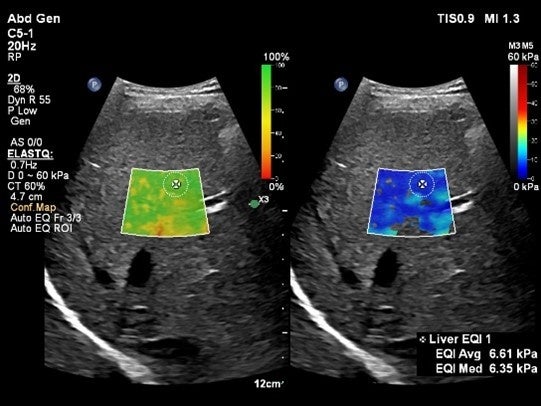

2. Auto ElastQ(オート・エラストキュー)

Shear Wave Elastographyを用いて肝臓の硬さを非侵襲的に計測するアプリケーションElastQ(エラストキュー)に、自動化機能が追加されました。Auto ElastQは、計測に適したフレームやROIポジションを自動で判別し、計測結果を表示することが可能です。これにより、これまで課題であった検査時間を最大60%短縮し[2]、99%の再現性が報告されています。[3]